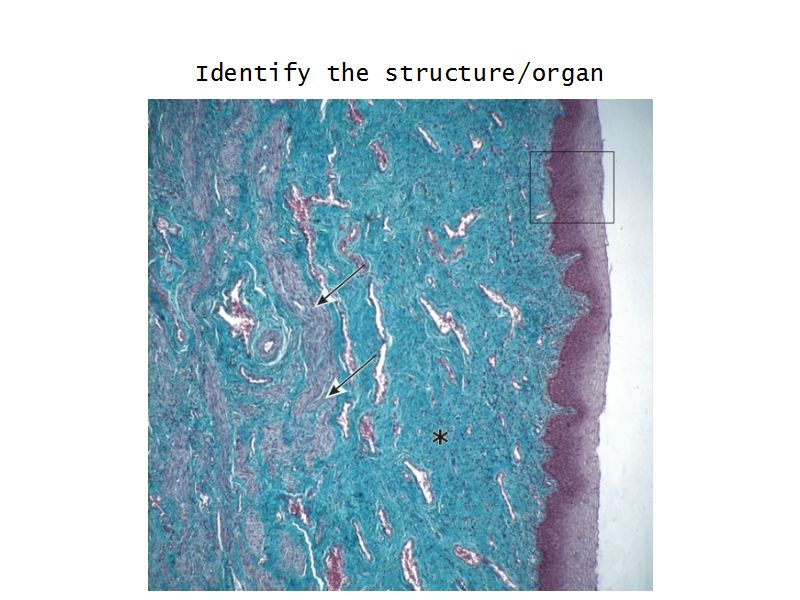

Vagina

Slide 90

Vagina

- Fibromuscular tube with 3 layers

- Inner mucosa

- Middle muscle layer

- External adventitia

Fibro = fibrous tissue

Muscular = muscle tissue

Tube = epithelium

Mucosa

- Epithelium

- Thick stratified squamous nonkeratinized

- Lamina propria

- Fibroelastic connective tissue

- Rich in elastic fibres

- Contains lymphoid elements

- Deep portion highly vascular

- No glands

Muscle layer

- Thin inner circular

- Thick outer longitudinal

- External orifice ring of skeletal muscle

Adventitia

- Fibroelastic connective tissue

- Fixes onto surrounding structure

- Blood vessels and nerves